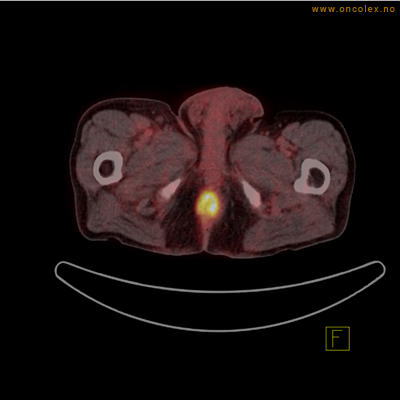

PET/CT (PET: Positron Emisjons Tomografi/ CT: Computer Tomografi) er en avansert nukleærmedisinsk bildetakingsmetode. Metoden er et godt dokumentert, veletablert og svært nyttig verktøy i bildediagnostikk ved kreft. Et PET-kamera gir tredimensjonale bilder av hele kroppen. Integrert CT gjør at informasjonen fra PET blir lokalisert anatomisk nøyaktig.

Kort beskrivelse av undersøkelsen

Gjennom en nål (plastkanyle) i en blodåre i armen vil du få et radioaktivt stoff. Det mest vanlige er radioaktivt druesukker (18F-FDG). Stråling fra det radioaktive stoffet registreres i PET-skanneren og viser hvordan dette stoffet fordeler seg i kroppen. Det normale opptaket av det radioaktive stoffet vil være endret ved sykdomsprosesser. Celler med høyt stoffskite, som for eksempel kreftceller, har økt opptak av sukker. Ved undersøkelsen kan man dermed ofte se større opptak av det radioaktive sporstoffet i kreftsvulster.  Siden CT tas samtidig, kan PET og CT bildene legges sammen og vise nøyaktig hvor i kroppen det økte opptaket er.

Eksempler på funn

Vev som tar opp mer radioaktivt stoff, synes som hvite områder som lyser opp mer i forhold til annet vev som tar opp mindre sukker.